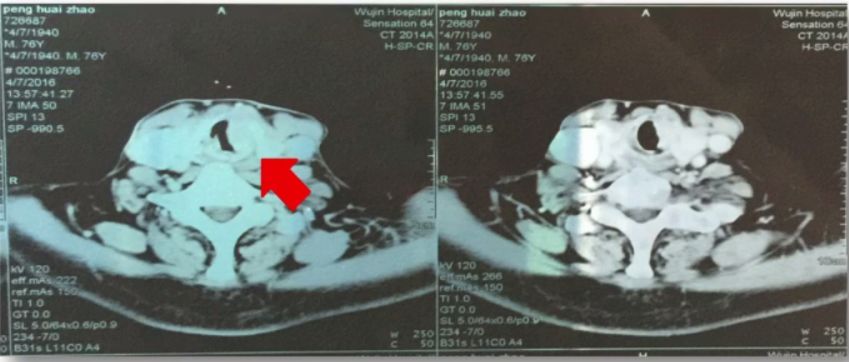

颈部CT

甲状软骨水平气道受阻,喉肿物